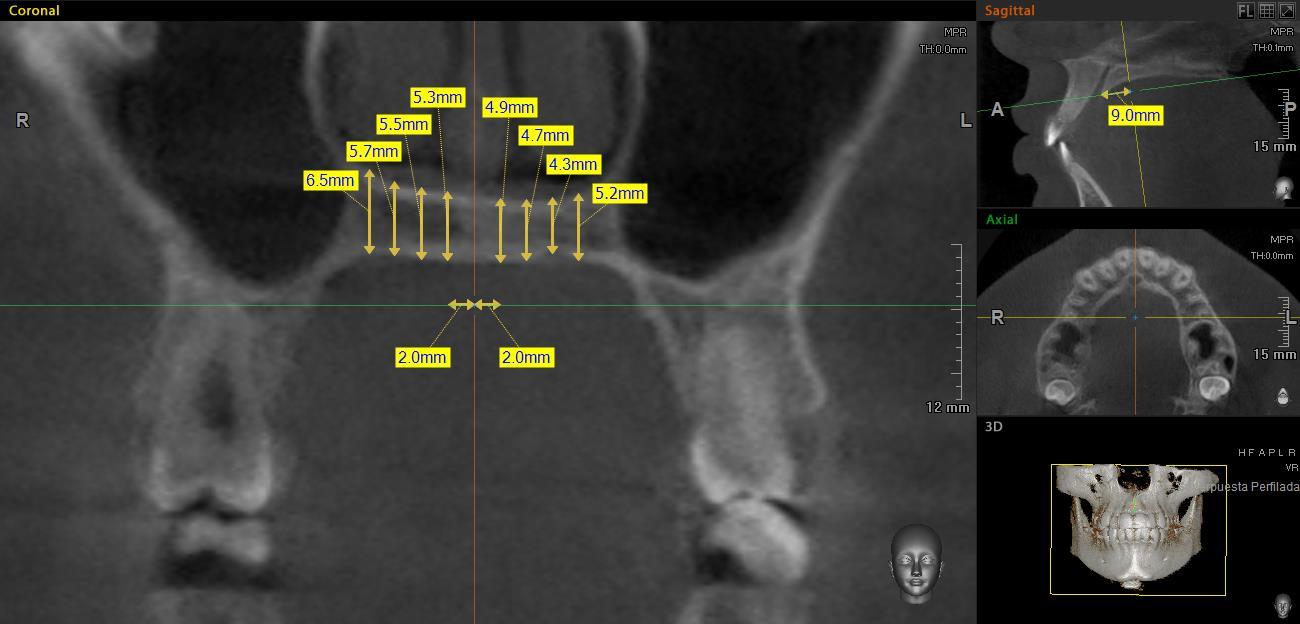

En el corte sagital, las mediciones se realizaron de los 0 a los 24mm, con intervalos de 3 mm entre cada una, con la primera medición en el borde posterior del foramen incisivo (Figura 2). Las mediciones del grosor palatino se realizaron en el corte coronal a los 2, 4, 6 y 8mm, de la sutura media palatina hacia ambos lados (Figura 3).

Posteriormente, en el corte coronal (Figura 3), perpendicular al plano axial se tomaron las medidas del grosor palatino en cada uno de los puntos de intersección de las líneas de referencia antes mencionadas, formando una cuadrícula de 72 sitios (Figura 4). Así, en las Figuras 3 y 4 se observa el grosor palatino de 5.3mm a los 2mm (sagital) y 9mm (coronal) del lado derecho.

Grosor palatino medido a los 9mm del borde posterior del foramen incisivo